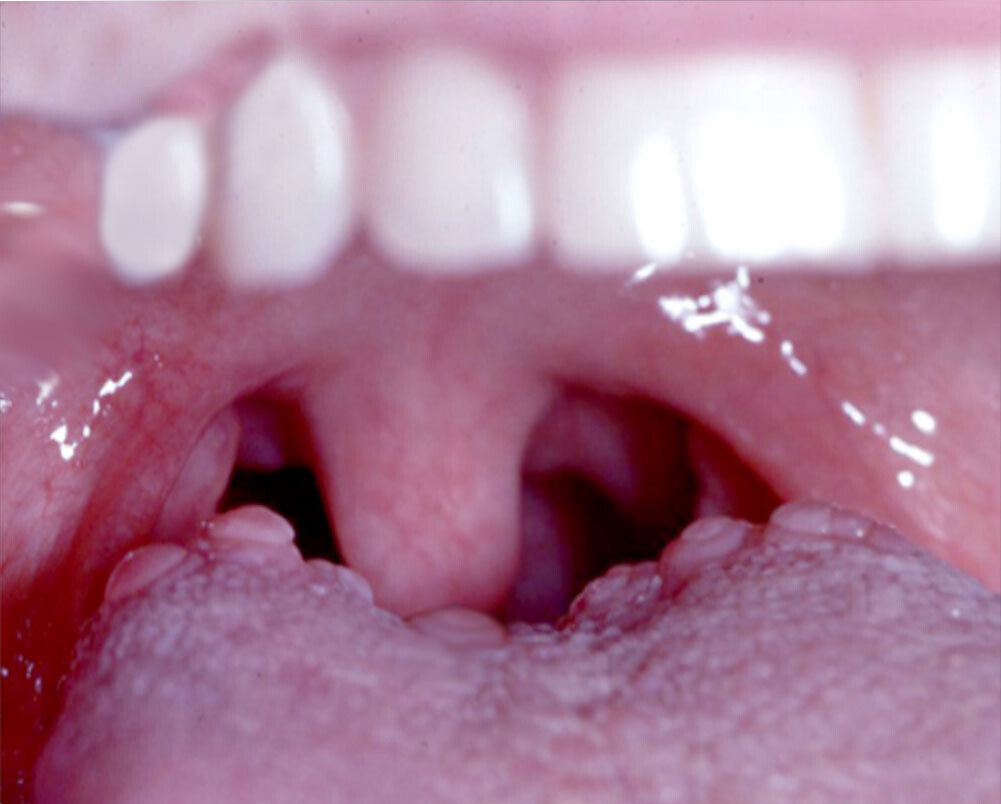

What Causes Red Spots On The Roof Of Your Mouth?

Red spots on the roof of your mouth can be caused by a variety of different reasons. Some are just a minor inconvenience, while others could be a sign of a more serious health issue that may require further investigation. Here are some common possibilities:

Coxsackievirus

The virus behind hand, foot and mouth disease, coxsackievirus can cause painful blisters and red spots on the roof of the mouth, as well as on the hands and feet. It is most common in children under five years of age, but does occur in people of all ages. Treatment options include over-the-counter medications for fever and pain, as well as special medicated mouthwashes to help alleviate the discomfort associated with the oral sores.

In rare cases, oral sores or lesions can be a sign of oral cancer, so it is important to have any spots that are painful, cause difficulty in eating or drinking or do not heal quickly checked by your dentist.